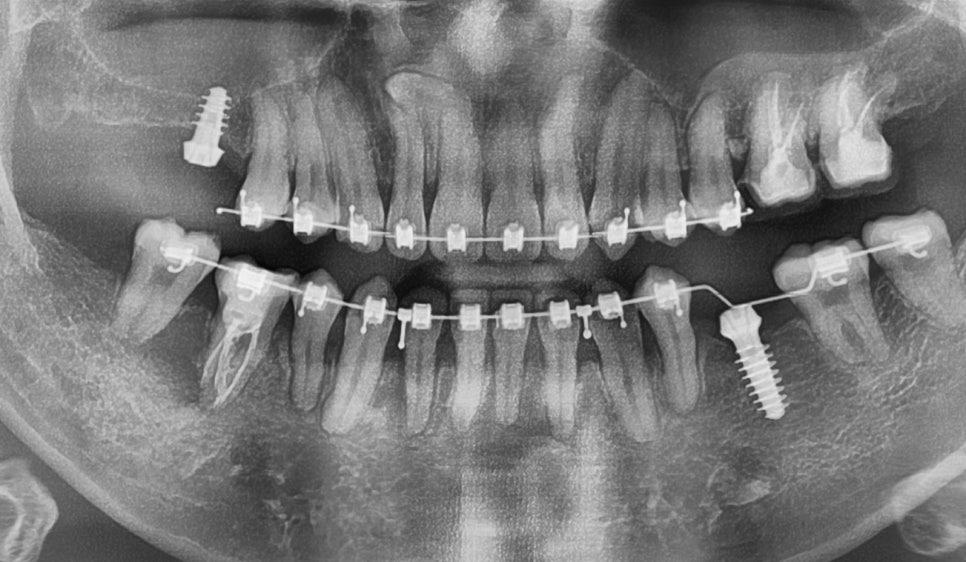

25.04.07

25.04.28

임플란트 식립 시에는 주변 치아와의

조화를 고려해서 위치와 각도를

정밀하게 결정합니다.

25.06.02

최종적으로 보철물을 장착할 때도

전체적인 교합을 고려해서

제작하게 됩니다.